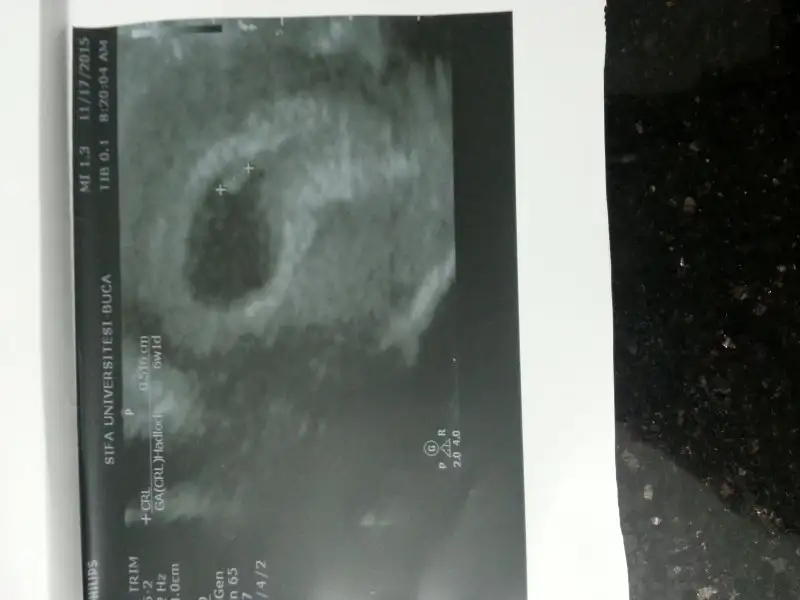

Canım ben bu usg resimlerini kız olarak yorumluyorum. Fakat bizimki sadece tahmin. İleri ki haftalarda en doğru sonucu doktorunuz verecektir.merhaba cnm.tesadüfen buradayım.paylaşımın çok ilginç geldi rica etsem benim usg görüntülerümi de yorumlar mısın?..2 farklı dr un,3 gün arayla muayenesi.birine göre 7+1 haftalık görünüyorum.diğerne göre 8+0 sata göre ise 8+2 olamlıydım o gün..Eki Görüntüle 1713739 4 boyutlu,7+1 de bz işey anlayamadık bundanEki Görüntüle 1713740 7+1 normal görüntüEki Görüntüle 1713741 bu da üstteki konrtrolden sonra başka ir dr un usgsi.8+0 .sata göre bu görüntülerde 8+2 olmalıydım.

cnm ben plasenta ortada demiştin ya.bir resim daha buldum bakabilir misiiin ?bu da 6+2 karından usg .6 veya 7 haftalık ultrason görüntüsü lazım. bir de karından mı yoksa vajinal mi ultrasonun belirtirsen sana da tahmin de bulunuruz.

burda biraz daha belirgin plasenta sağa meyilli karından usg olduğuna göre yüksek ihtimal kız bebek canım.cnm ben plasenta ortada demiştin ya.bir resim daha buldum bakabilir misiiin ?bu da 6+2 karından usg .